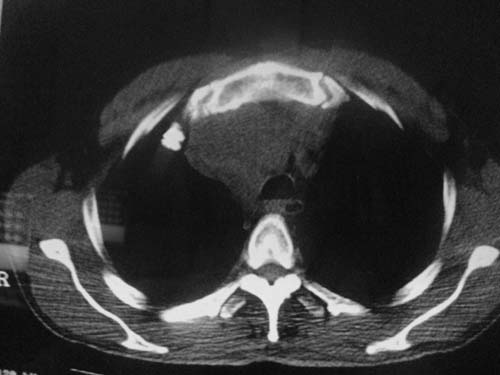

以下是引用科室第一人在2010-3-25 20:30:00的发言:[br]1:纵膈肿瘤性病变,恶性胸腺瘤可能性大伴纵膈右肺门淋巴结转移,右侧胸腔积液。[br]2:右侧肺门肿瘤性病变,纵膈淋巴结转移,右侧胸腔积液。右下叶转移。

以下是引用子期在2010-3-25 21:00:00的发言:[br]先考虑右中央型肺癌伴转移。

以下是引用江广1996在2010-3-25 22:49:00的发言:[br]通常肺癌向纵隔转移多见,纵隔肿瘤向肺内转移少见(有的表现为向肺内侵润)。本例以一元论考虑:右中心型肺癌并纵隔淋巴等多处转移。[br][br][本贴已被 江广1996 于 2010-3-25 22:50:07 修改过]

以下是引用yangyudong333在2010-3-26 6:43:00的发言:[br]“冰冻纵膈”,考虑纵膈淋巴瘤伴肺内及胸膜侵润。